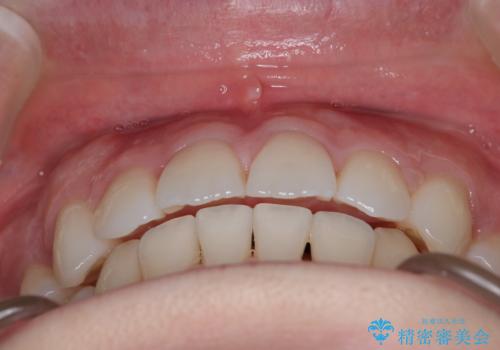

- 出っ歯を主訴に来院されました。今回は4番の歯を4本抜歯をし、ワイヤー矯正にて治療しました。

抜歯矯正のため2年を予定してましたが、予定よりも早く終わることができました。また口元も下がり、かみ合わせも改善しました。